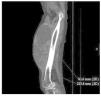

Sarcoma de partes blandas

La aparición de una tumoración de partes blandas, especialmente en las extremidades, puede corresponder a un sarcoma. Aunque son formas de neoplasia poco frecuentes, debemos conocerlas para no demorar el diagnóstico. La clínica inicial suele corresponder a una tumoración no dolorosa y de crecimiento rápido. El tratamiento de elección es quirúrgico, de forma ocasional de radioterapia y/o quimioterapia, que globalmente consiguen una curación del 50%.